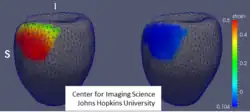

Surface estimation in cardiac computational anatomy

Numerous studies have now been done on cardiac hypertrophy and the role of the structural integraties in the functional mechanics of the heart. Siamak Ardekani has been working on populations of Cardiac anatomies reconstructing atlas coordinate systems from populations.[34][35][36] The figure on the right shows the computational cardiac anatomy method being used to identify regional differences in radial thickness at end-systolic cardiac phase between patients with hypertrophic cardiomyopathy (left) and hypertensive heart disease (right). Color map that is placed on a common surface template (gray mesh) represents region ( basilar septal and the anterior epicardial wall) that has on average significantly larger radial thickness in patients with hypertrophic cardiomyopathy vs. hypertensive heart disease (reference below).[33]